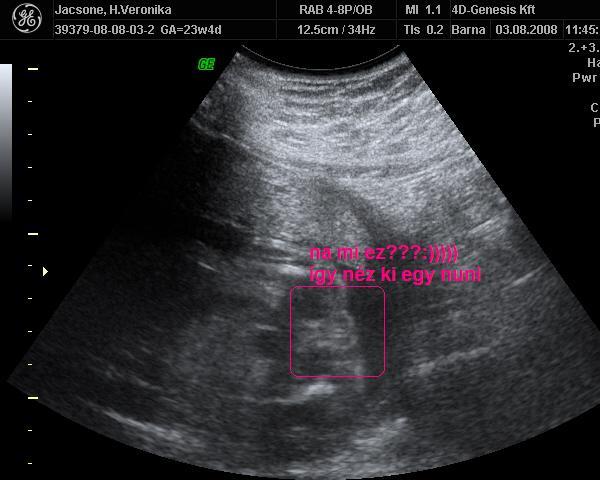

Mikor Én voltam a genetikán uh-on ,akkor csináltak 4d képet 4000ft/db-ért